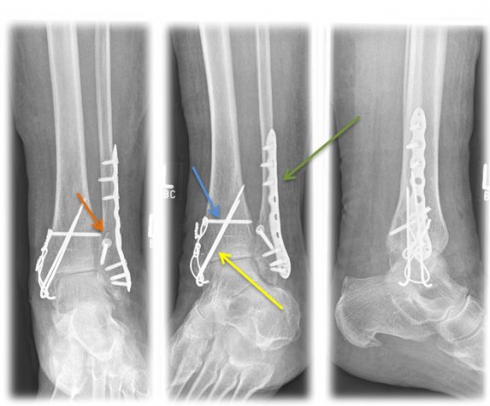

Method of choice in surgical therapy

- Internal ankle fracture: mostly use of cannulated screws or tension belt osteosynthesis

- Outer ankle fracture: usually insertion of a lag screw and a neutralization plate

- tape seam may be necessary if the inner tape can be folded out

- In case of syndesmosis injury, the insertion of an adjusting screw is necessary for 6 weeks to stabilize the syndesmosis.

Fig. 4) Osteosynthetic treatment of a bimallel ankle fracture by means of tension belt osteosynthesis at the inner ankle (yellow arrow), neutralization plate (green arrow) and a traction screw (orange arrow) at the outer ankle as well as an adjusting screw (blue arrow).